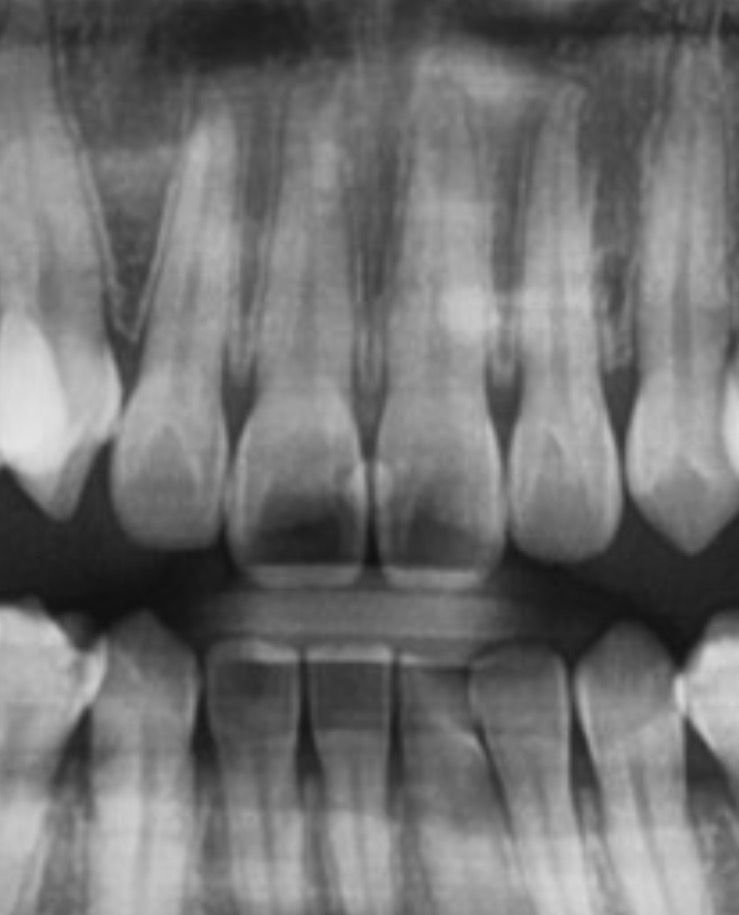

앞니 사이 충치 레진한 부분 치실했는데 조각 같은게 나왔어요(사진 첨부)

레진은 뒷면에서 했는데 앞에서 보면 뭔가 있어서 신경쓰였거든요

두 장은 어제 찍은 사진이에요..

• 2번 째 사진

레진이 떨어진 것으로 보이진 않고 레진 접착제가 치아 사이에 있진 않습니다. 이물질 같습니다.

수복후에도 치실이 들어가야 원래는 정상입니다. 안들어갔다면 치아 사이가 붙어있었다는 이야기인데 아마 말씀을 들어보니 레진끼리 붙은겉은 아니고 레진 접착제가 치아 사이에 달라붙어서 연결되어있었던 것 같은데요. 사진상으로 보기에는 레진 자체에는 큰 문제는 없는 것으로 봐서 아마도 레진접착제였을 가능성이 가장 높겠습니다.

레진조각 일부가 떨어졌을 가능성이 높으며, 레진 충전물은 시간이 지나면 마모가 되어 일부 떨어질수 있습니다. 현재 사진상 크게 문제가 있어 보이지는 않으나, 걱정이 되는 경우에는 치과에 방문하여 검진을 받아보길 권합니다.

레진이 떨어지거나 하진 않은 것 같고요. 레진 붙이기 전 전처리 시의 접착제 잔여물일 수 있을 것 같습니다.

레진을 하고 난다음에 레진 조각이 탈락할수도 있습니다

사진으로 봤을 경우에는 크게 문제가 보이지는 않습니다.